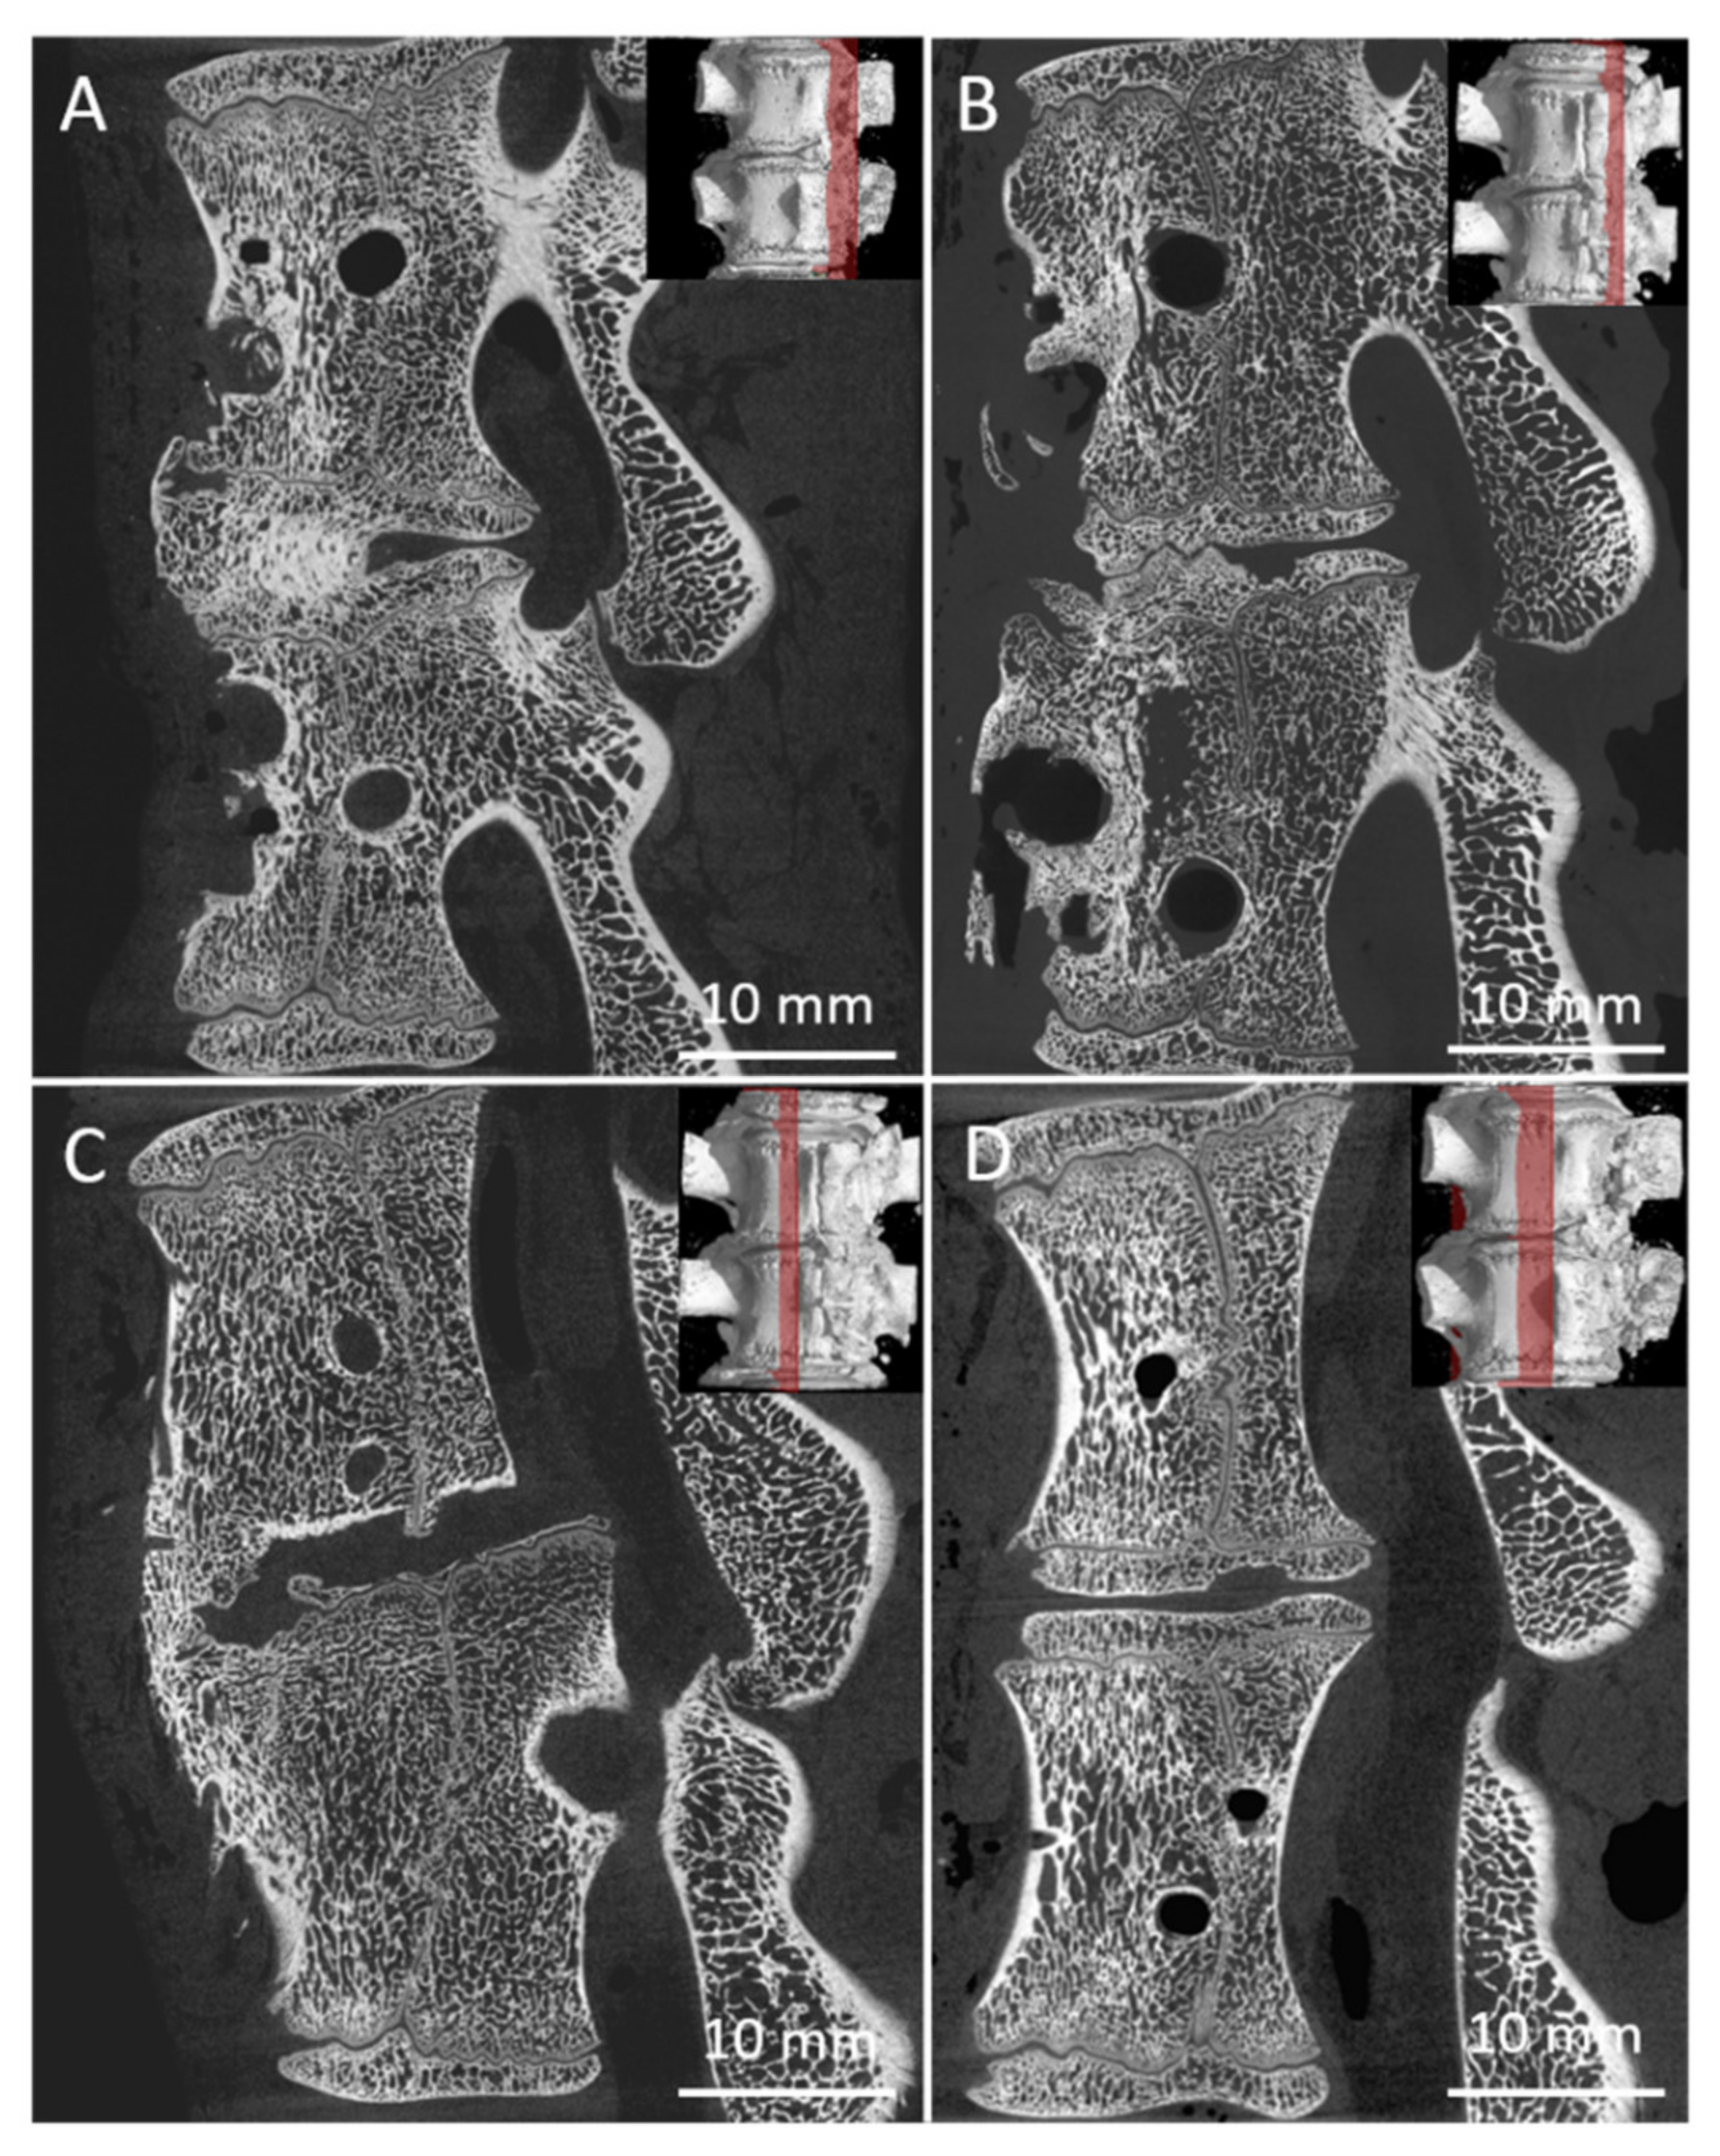

There were 24 measurements performed in both groups, twelve for each group A (A1, Figure 9A; A2 Figure 9B) and B (B1, Figure 9C; B2, Figure 9D). All harvested spine samples from subgroups after 8 and 16 weeks were scanned immediately after pig euthanasia.

Figure 9.

Sagittal micro-CT sections of the middle part of 6 samples from the Group A1 (A), Group A2 (B), Group B1 (C), and Group B2 (D), of the L2/3 section of pig spines. The plane of the section is recorded by a red line on the 3D reconstruction of the spine model.

Samples were classified by the mentioned grading system, and the results of the analysis are in Table 1. Table 1 summarizes the results of the fusion assessments at the study endpoint after 8 and 16 weeks. After 8 weeks, we observed a similar distribution of fusion quality in both groups, without statistically significant difference. On the contrary, in group B, the results after 16 weeks showed the presence of fusion grade 1 or 2 in 6 specimens, while the number of samples in group A did not change.

As can be seen from Table 1, the 8-week bone autograft group (subgroup A1) involved three samples, where the vertebras were surprisingly fused within the whole area of the bone graft. The fusion is steady and compact in micro-CT cross-sections. In one case, the bone graft was already fully absorbed exhibiting no fusion at all. However, after 16 weeks, the second group of bone grafts (subgroup A2) displayed a much lower quality of fusion, where the graft was completely absorbed in three cases. The vertebrae fused around the bone graft, and the fusion caused so-called non-union outgrowth around the whole vertebra’s body (Figure 10A). These large outgrowths have mostly affected the motion and bending of the spine. Moreover, intervertebral endplates are missing since they have been absorbed during the interaction with the bone graft. These disadvantages are widespread when a bone autograft is used.

As for the 8-week subgroup B1, where BHI was applied, the demonstrated results in Table 1 are very similar to subgroup A1. However, except for one fully absorbed sample, the fusion was mainly generated through/over the scaffold. Clearer are data from the 16-week subgroup B2, where fusions appear only between the bodies of the vertebra, and no large outgrowths were visible around the vertebrae in micro-CT images (Figure 10B). In addition, the intervertebral endplates were still found within the images, and in a few cases, intervertebral plate narrowing was observed.